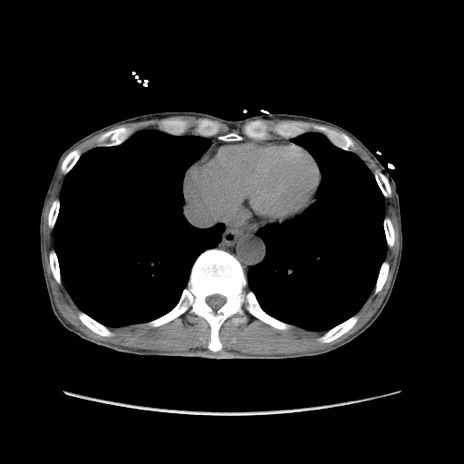

症例11(横断像)

【症例】 60歳代男性

【主訴】 下腹部痛

【現病歴】 本日夜中より下腹部痛の症状認め、受診。

【既往歴】 膀胱癌(膀胱全摘+尿管皮膚瘻術) 、胃癌術後

【身体所見】 BT 35.3℃、PR 58/min、BP 136/98mHg、腹部平坦、軟、腸蠕動音±、ストマ留置あり、左上腹部~正中部に圧痛あり、反跳痛なし。

【データ】WBC 5100、CRP0.01